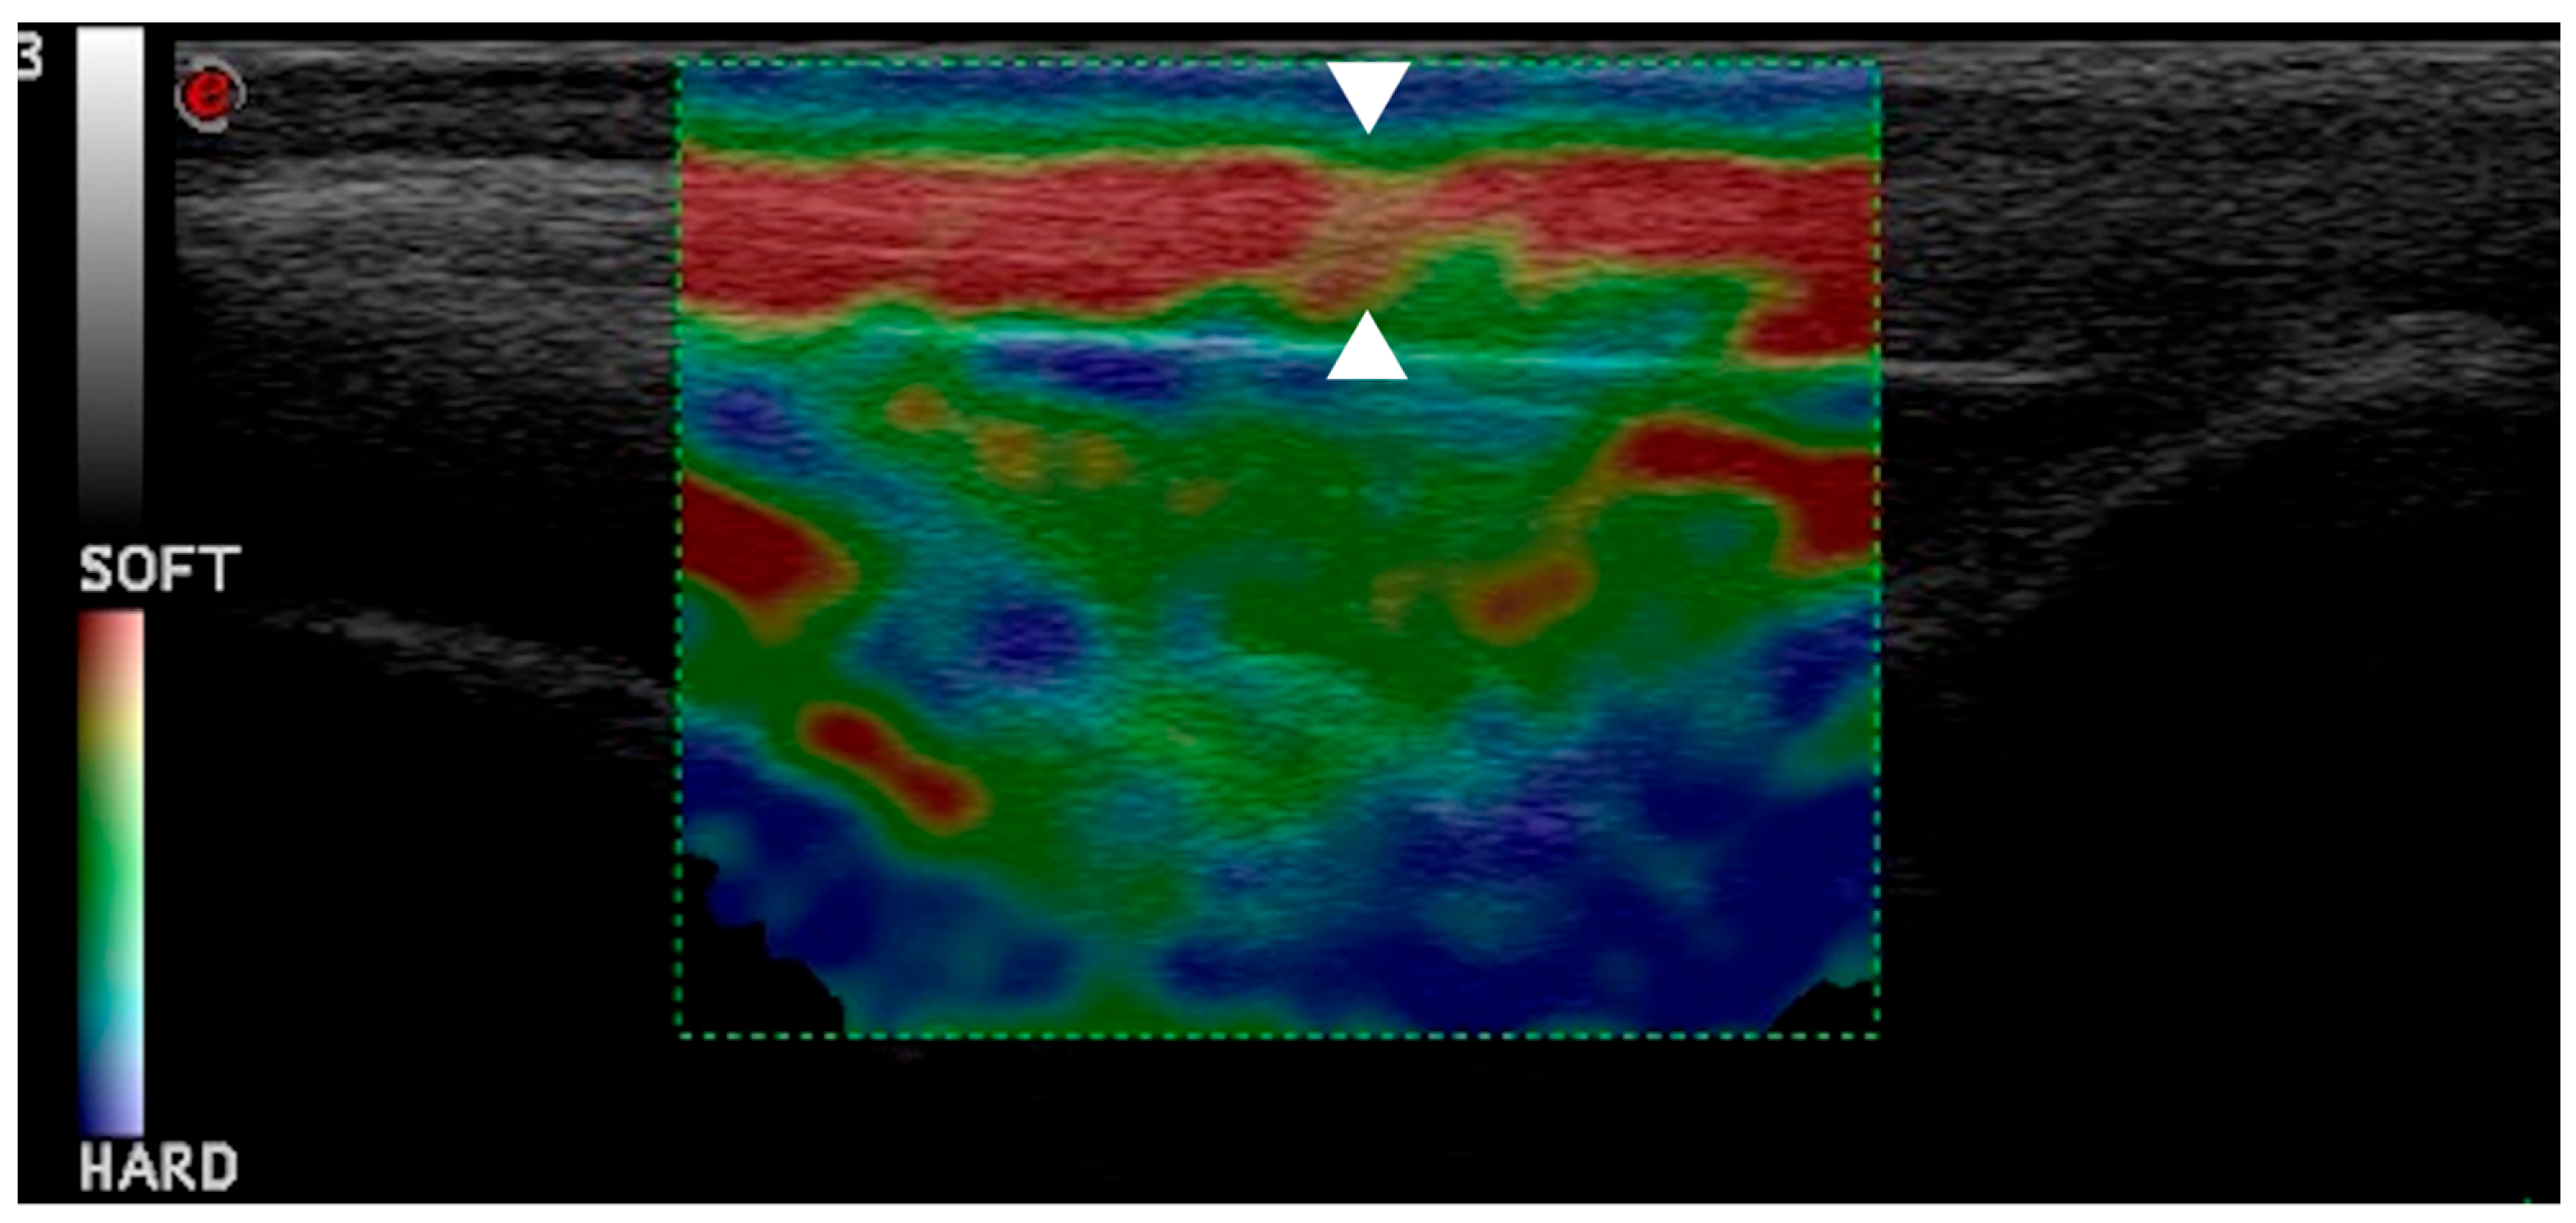

Figure 7.

This elastogram shows green and yellow areas with red coloring, indicating hardening of patellar ligament one month post-TPLO (arrowheads).